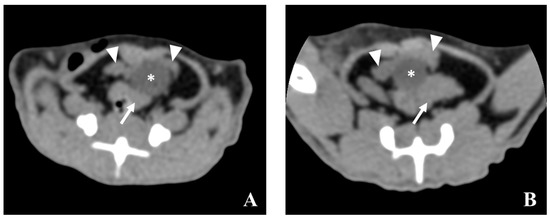

5.2. Computed Tomography (CT)